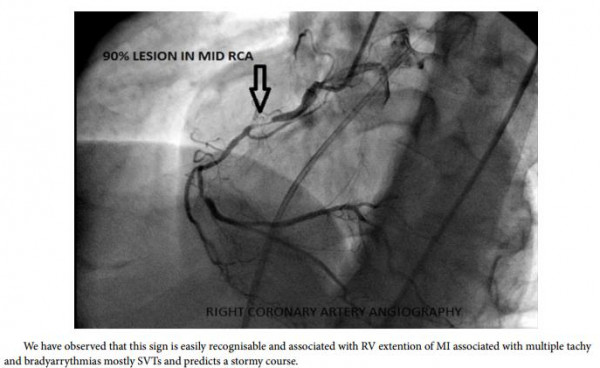

وأوضح الدكتور أيمن خيري نائب مدير المستشفى لشئون الجودة أن المستشفى قد استقبلت المريض الذي يبلغ من العمر 36 عاما ويعمل مسعفاً بمستشفى المبرة يعانى من توقف بالقلب والذي تبين أنه يرجع إلى انسداد تام فى الشريان التاجي الأيمن نتيجة حدوث تجلط شديد.

واشار إلى أنه على الفور تم عمل جهود مكثفة لإسعافه وإنعاش القلب عن طريق الصدمات الكهربية مع إتخاذ قرار عاجل بإجراء قسطرة وتركيب دعامة دوائية لإنقاذه حتى تم الاطمئنان على عودة القلب للنبض مرة أخرى ثم استقرار حالته الصحية مشيداً بما بذله الفريق الطبي المتميز فى إنقاذ حياة المريض والذي ضم الدكتور محمد على المدرس بقسم أمراض القلب والدكتور محمد أبو الحسن، ومحمد عثمان المدرسين المساعدين بالقسم والطبيبان أسماء جلال وخالد صابر النواب بالمستشفى.